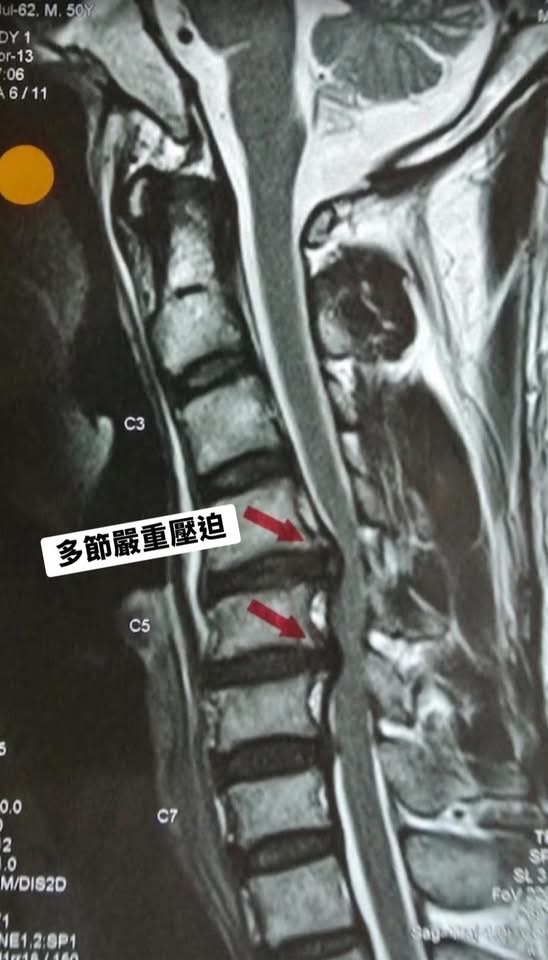

在脊椎醫學的世界裡,精準的影像分析是治療的靈魂。當我將她那張顯示嚴重壓迫的 MRI 影像放大(如圖紅色箭頭處),逐一解釋神經受壓的機轉時,Sofia 眼神中的迷惘轉化成了安心。她終於知道自己的壓迫確實很嚴重,但因為她沒有大小便失禁!手腳很痛但還是有力氣,重點是她肌肉還沒有萎縮